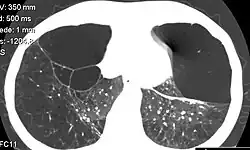

| CT scan of the lung showing bullae in the lower lung lobes of a subject with type alpha-1-antitrypsin deficiency. There is also increased lung density in areas with compression of lung tissue by the bullae. | |

A focal lung pneumatosis is an enclosed pocket of air or gas in the lung and includes blebs, bullae, pulmonary cysts, and lung cavities. Blebs and bullae can be classified by their wall thickness.[1]

- A bleb has a wall thickness of less than 1 mm.[2] By radiology definition, it is up to 1 cm in total size.[3] By pathology definition, it originates in the pleurae (rather than in the lung parenchyma).[4]

- A bulla has a wall thickness of less than 1 mm.[2] By radiology definition, it has a total size of greater than 1 cm.[3] By pathology definition, it originates in the lung parenchyma (rather than in the pleurae).[4]